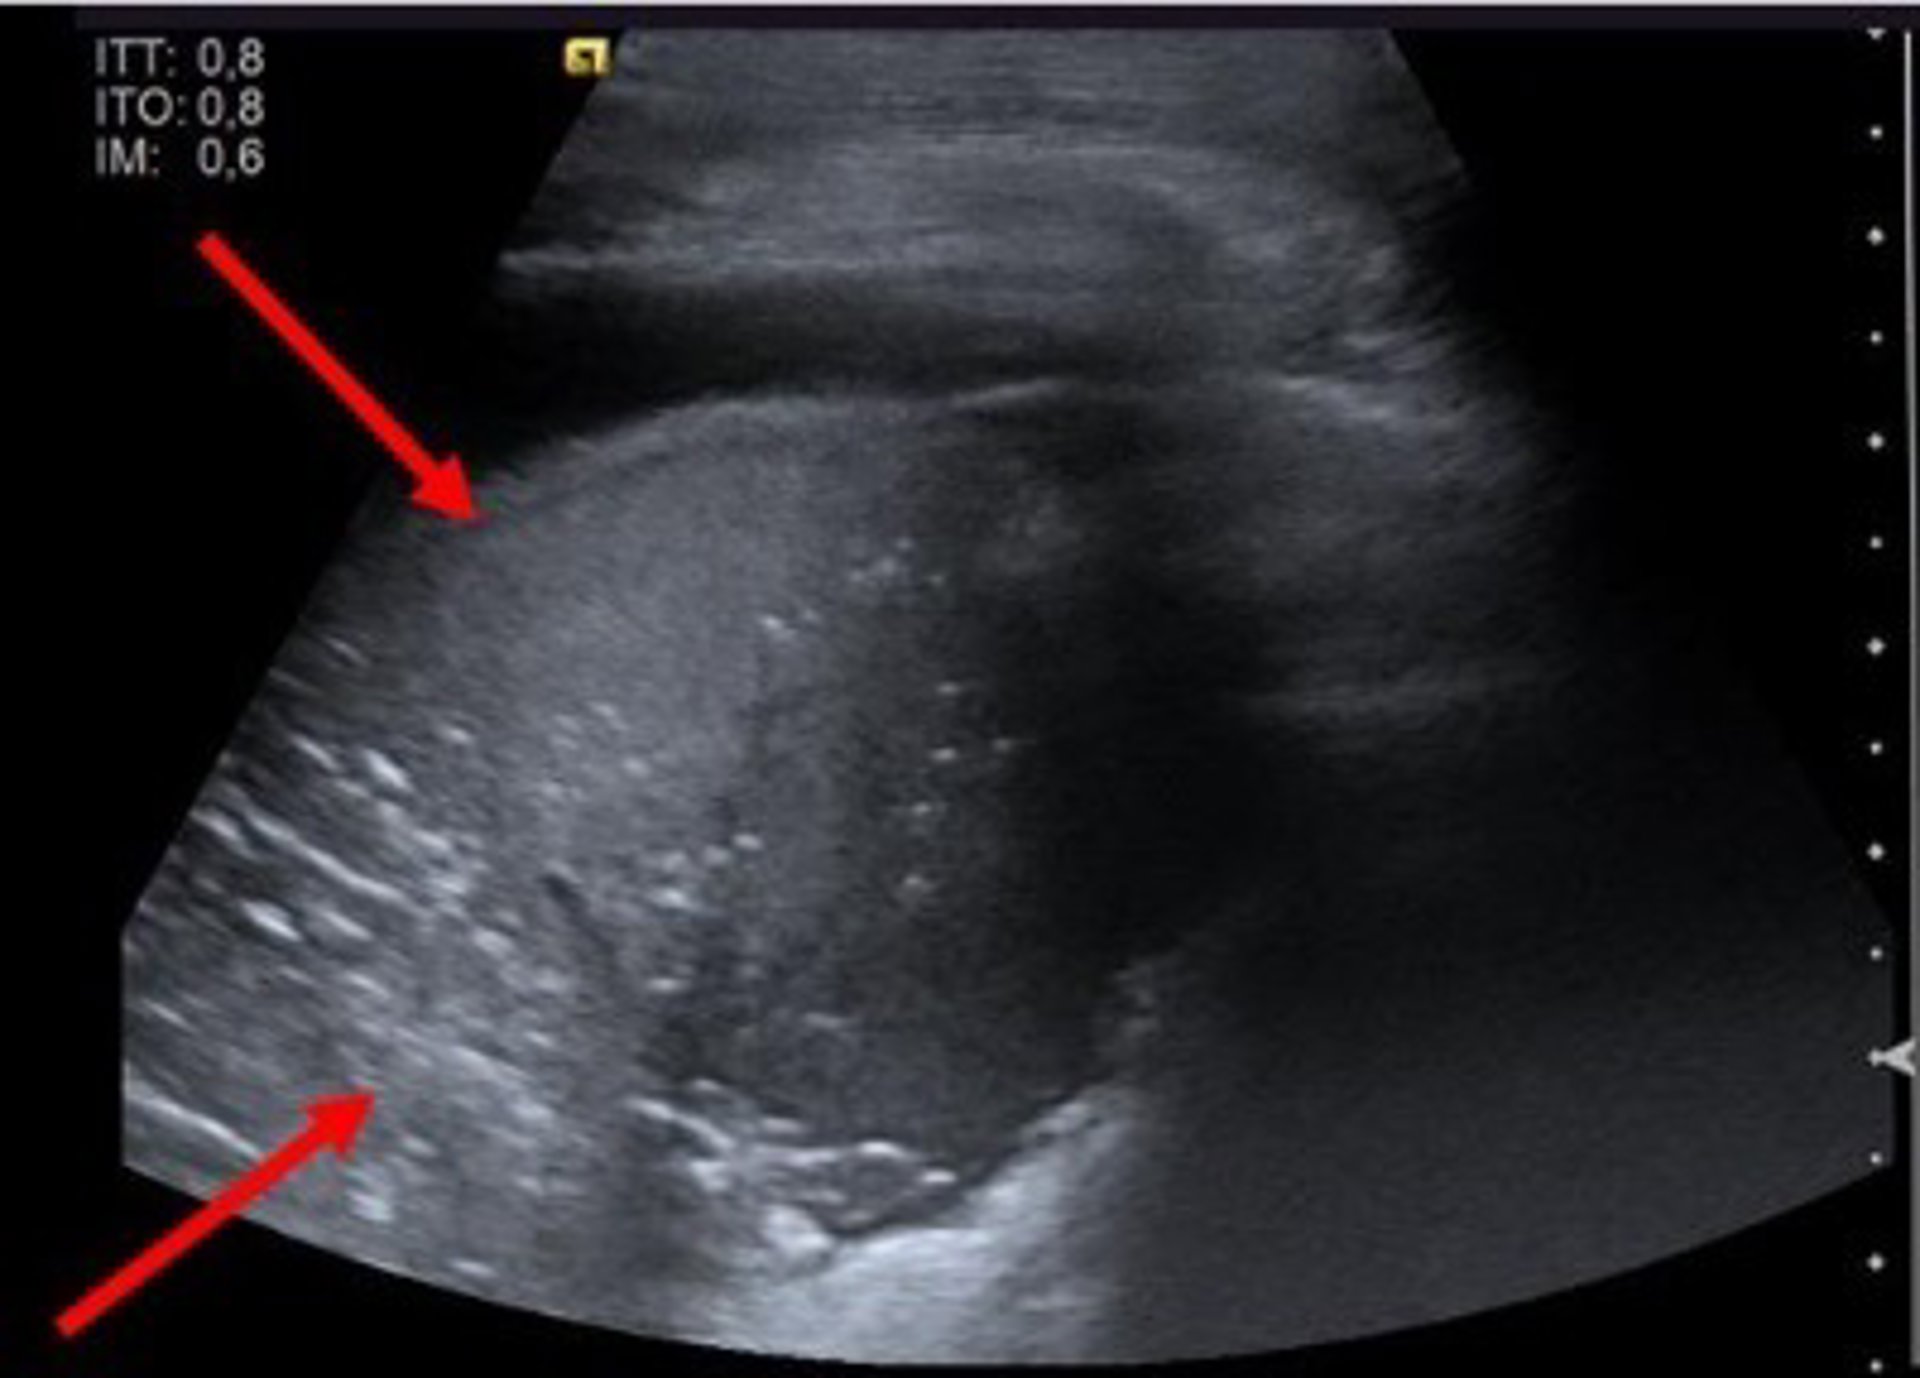

Imagen incluida Suplemento COVID 19 EuroEco - SEMG

Y es que, los pacientes con Covid-19 presentan un patrón ecográfico característico: adelgazamiento de la línea pleural con irregularidad de la misma; múltiples líneas B con variabilidad de patrones; consolidaciones pulmonares; aparición de líneas A durante la fase de recuperación; y derrame pleural infrecuente.